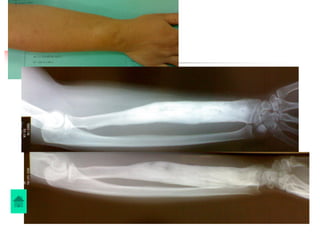

Giai đoạn mãn tính

Viêm xương chấn thương

Chẩn đoán

Lâm sàng:

Dò mủ kéo dài, đau nhức ít, không sốt hoặc sốt âm

ỉ, sưng nề khu trú

Xquang: Có thể thấy xương chết, xương tù, phản

ứng tạo xương ngoài màng xương

Chụp Xquang đường dò có cản quang: thấy được

ngóc ngách của đường dò đi đến đâu